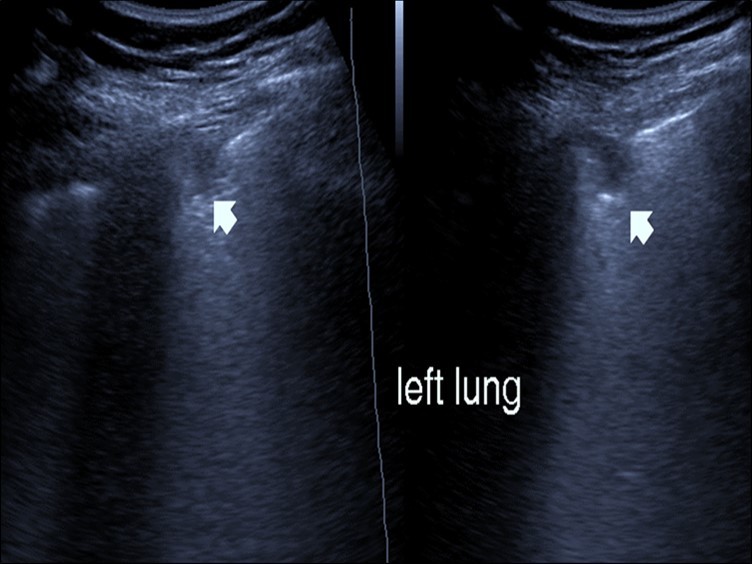

Bed side chest ultrasound may reveal positive findings as multiple Kerley’s B lines (>3 per intercostal space), pleural wall thickening (Figure 1), patchy areas of pulmonary consolidations especially in subpleural location (Figure 2, Figure 3) and obstructive lung collapse.

Figure 2.Chest ultrasound showing subpleural consolidation in patient with Covid-19.

Figure 3.Chest ultrasound showing right lung segmental consolidation with positive air bronchogram.